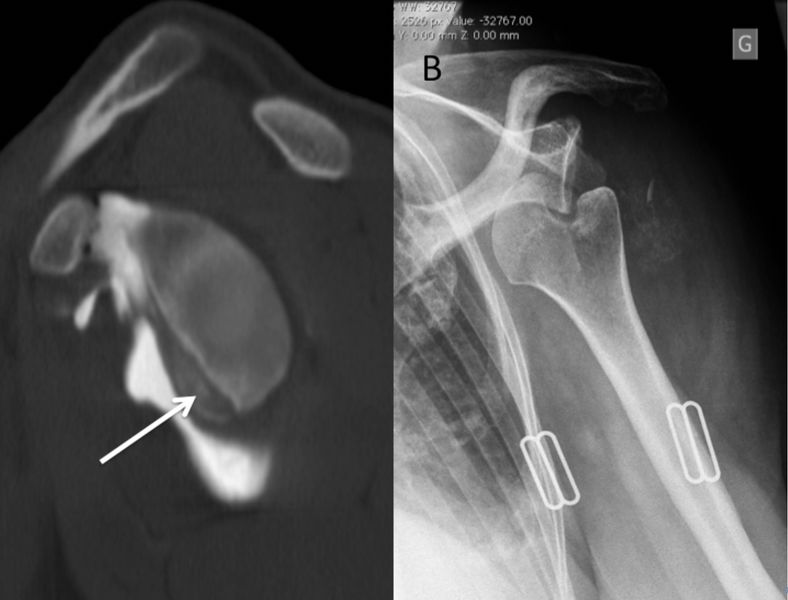

A) Sagittal view of a CT arthrogram of a left shoulder demonstrates a significant Bankart fracture that produces an “inverted-pear” glenoid. B) Plain anteroposterior radiograph reveals an anteroinferior glenohumeral dislocation with an “engaged” Malgaigne (Hill-Sachs) lesion of the humerus.